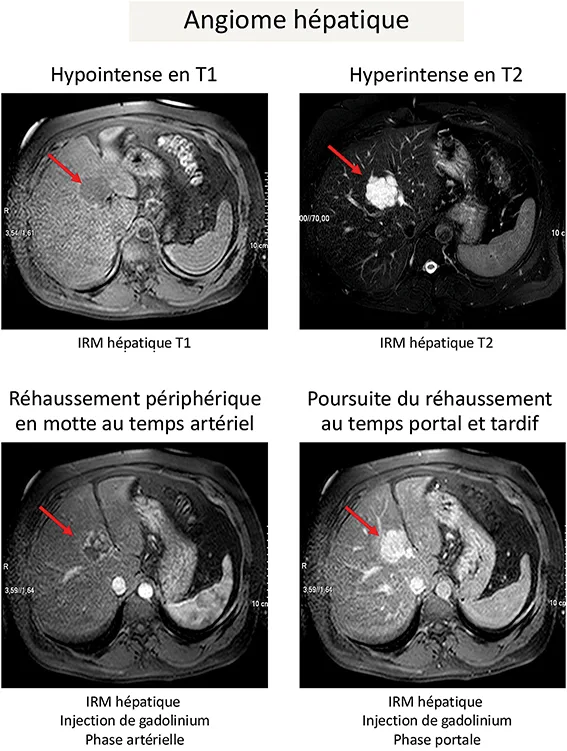

Hémangiome hépatique

Les hémangiomes hépatiques sont des malformations vasculaires se développant sur un foie sain. Il n’y a pas de différence en termes de ratio homme/femme, et il n’existe pas de lien avec la prise de contraceptifs à base d’œstrogènes ni avec la grossesse. Le diagnostic peut être posé par échographie hépatique, de manière non invasive, chez les patients sans maladie chronique du foie et sans antécédent de cancer, devant une lésion de moins de 2 à 3 cm, hyperéchogène, avec un renforcement postérieur (4). Pour les autres patients, un diagnostic non invasif peut être posé par une imagerie en coupe (IRM ou scanner avec injection de produit de contraste), mettant en évidence une prise de contraste progressive de la périphérie vers le centre, en mottes, du temps artériel au temps tardif (figure 1). Il n’y a pas de risque de complications et donc pas de nécessité de suivi ou de surveillance, quelle que soit la taille de l’hémangiome hépatique.

Figure 1 : Caractéristiques à l’imagerie (IRM hépatique avec injection de Gadolinium) d’un hémangiome hépatique